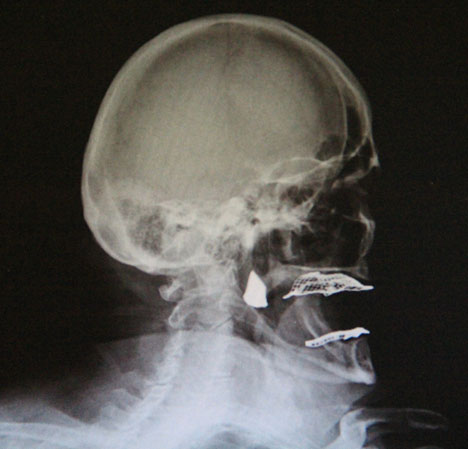

Yanağındaki ağrılardan şikayet eden 88 yaşındaki İshak İslamoğlu, yakınları tarafından Rize Devlet Hastanesi doktorlarından Genel Cerrah Salih Erkul’a götürüldü. Erkul, çekilen röntgende hastanın yanağında 3 cm çapında yabancı bir cisim tespit etti. Cismin tükürük bezlerine çok yakın olmasına rağmen Erkul tarafından gerçekleştirilen cerrahi müdahale ile cisim yerinden alındı. Hastanın yanağından çıkan 3 cm çapındaki yabancı cismin demir parçası olduğu anlaşıldı. Durum hasta yakınlarını ve doktoru şok etti.

İsmail İslamoğlu yaptığı açıklamada, yaklaşık 20 yıl önce bir kaza yaşadığını hatırlatarak, “Testere ile odun keserken birisi geçiyordu. Nazar etmiş olacak testere parçalandı. Yanağıma çarpan parçalar oldu. O gün bugündür yanağım hep ağrır. Gittiğim doktorlar pansuman edip ilaç verip gönderdi. Ağrılar artınca Salih beye geldik. Ameliyat ile yanağımdan demir parçasını çıkarttı” dedi.

Hastanın yanağından çıkan demir parçasının geçmişte parçalanarak hastanın yaralanmasına neden olan demir testereden kopan bir parça olduğu tahmin ediliyor.